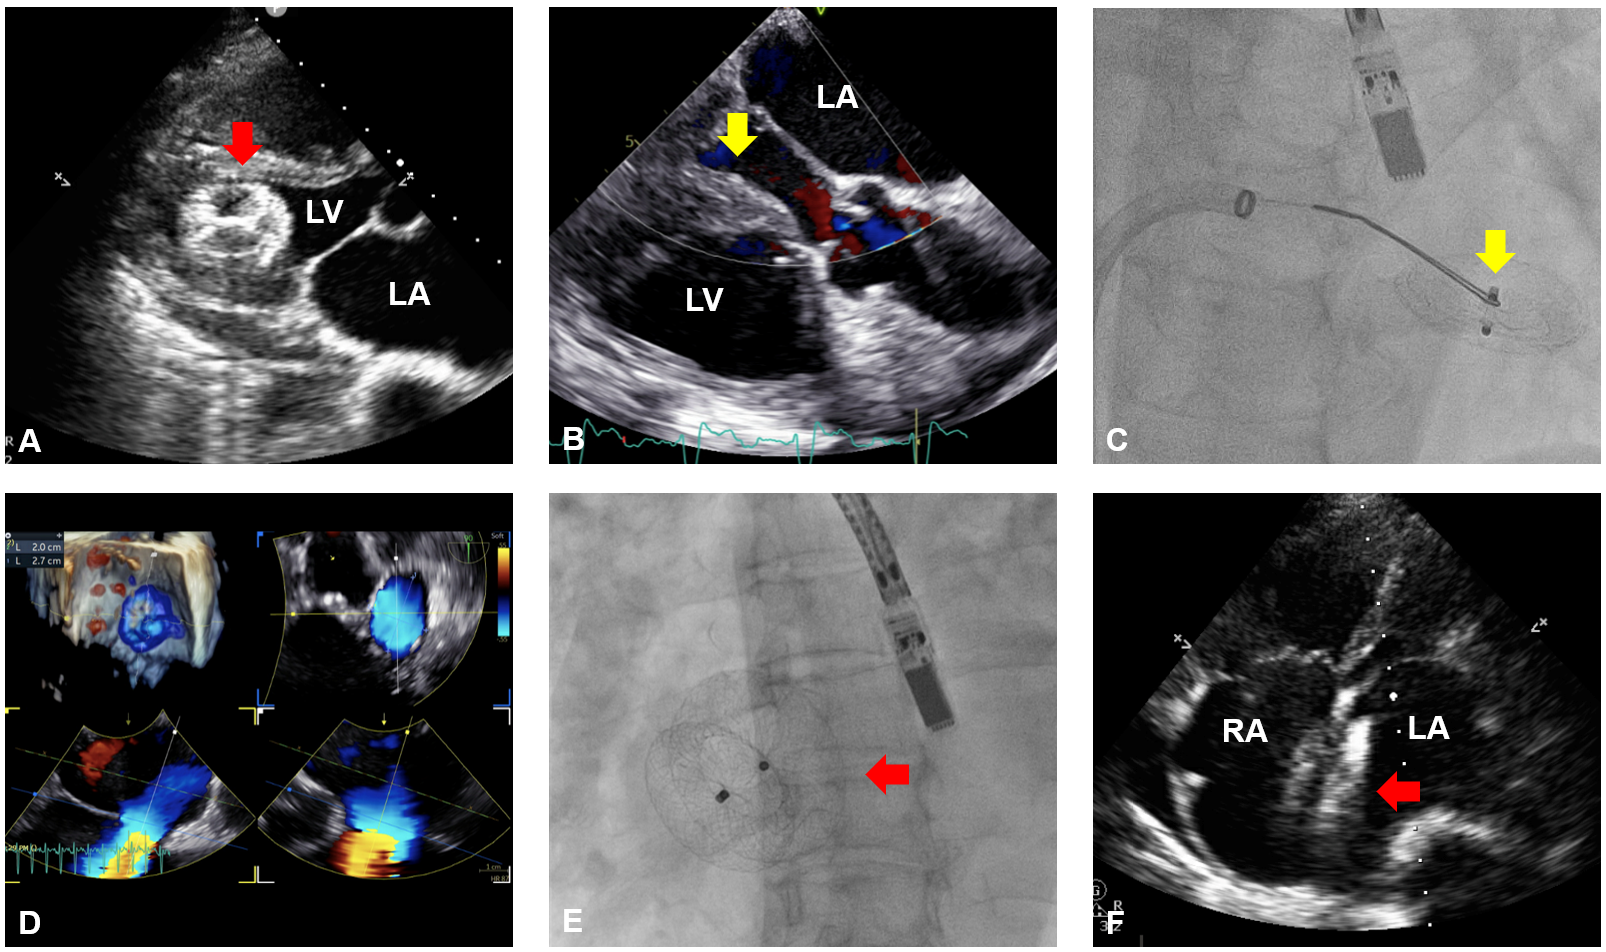

A 76-year-old woman with atrial septal defect (ASD) had previously undergone occluder implantation at another institution. At that time, preoperative transesophageal echocardiography (TEE) revealed an ASD measuring 2.0 x 2.5 cm with deficient retro-aortic rim. Transcatheter closure using a 24-mm Amplatzer Septal Occluder (Abbott) was performed. One month post-procedure, the device was found dislodged into the left ventricle (LV) (Figure A).

She was referred to our hospital for retrieval. The multidisciplinary heart team recommended percutaneous retrieval, reserving surgical treatment as a backup option. The procedure was performed under local anaesthesia with a 3-dimensional mini-TEE (9VT-D probe; GE Healthcare), which has a smaller tip for better tolerance under sedation. The connection hub of the occluder was found to face the mitral orifice, presenting a favorable orientation for antegrade retrieval (Figure B). A 14F Fustar steerable sheath (Lamed GmbH) was advanced into the left atrium through the ASD. Although a 9F sheath is minimally sufficient for a 24-mm occluder, a larger 14F sheath was chosen to ensure adequate oversizing. Subsequently, a 7F multipurpose angiographic catheter equipped with a 20-mm gooseneck snare was advanced into the LV (Video 1). The screw hub of the occluder was successfully snared (Figure C, Video 2), re-sheathed, and extracted.

Upon reassessment, the maximal ASD size was measured at 27 mm (Figure D). A 32-mm Amplatzer Septal Occluder was successfully implanted (Figure E). Echocardiography at 3 months demonstrated stable device positioning, absence of residual shunt, and trivial mitral regurgitation (Figure F).